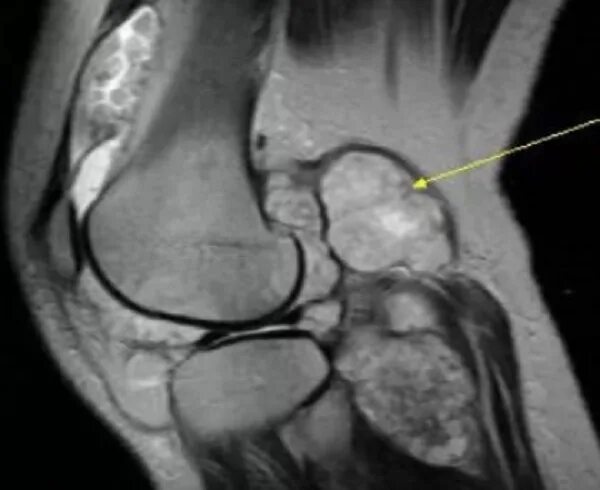

Синовиомы